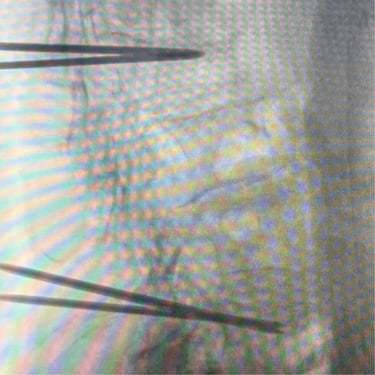

🧠Bloqueo lumbar selectivo en discopatía y espondiloartrosis: diagnóstico y alivio del dolor lumbar.

La discopatía degenerativa y la espondiloartrosis lumbar son causas frecuentes de dolor lumbar crónico. El bloqueo lumbar selectivo es un procedimiento mínimamente invasivo que permite identificar el origen del dolor y ofrecer alivio terapéutico mediante la administración dirigida de anestésicos y antiinflamatorios en las estructuras afectadas de la columna lumbar.